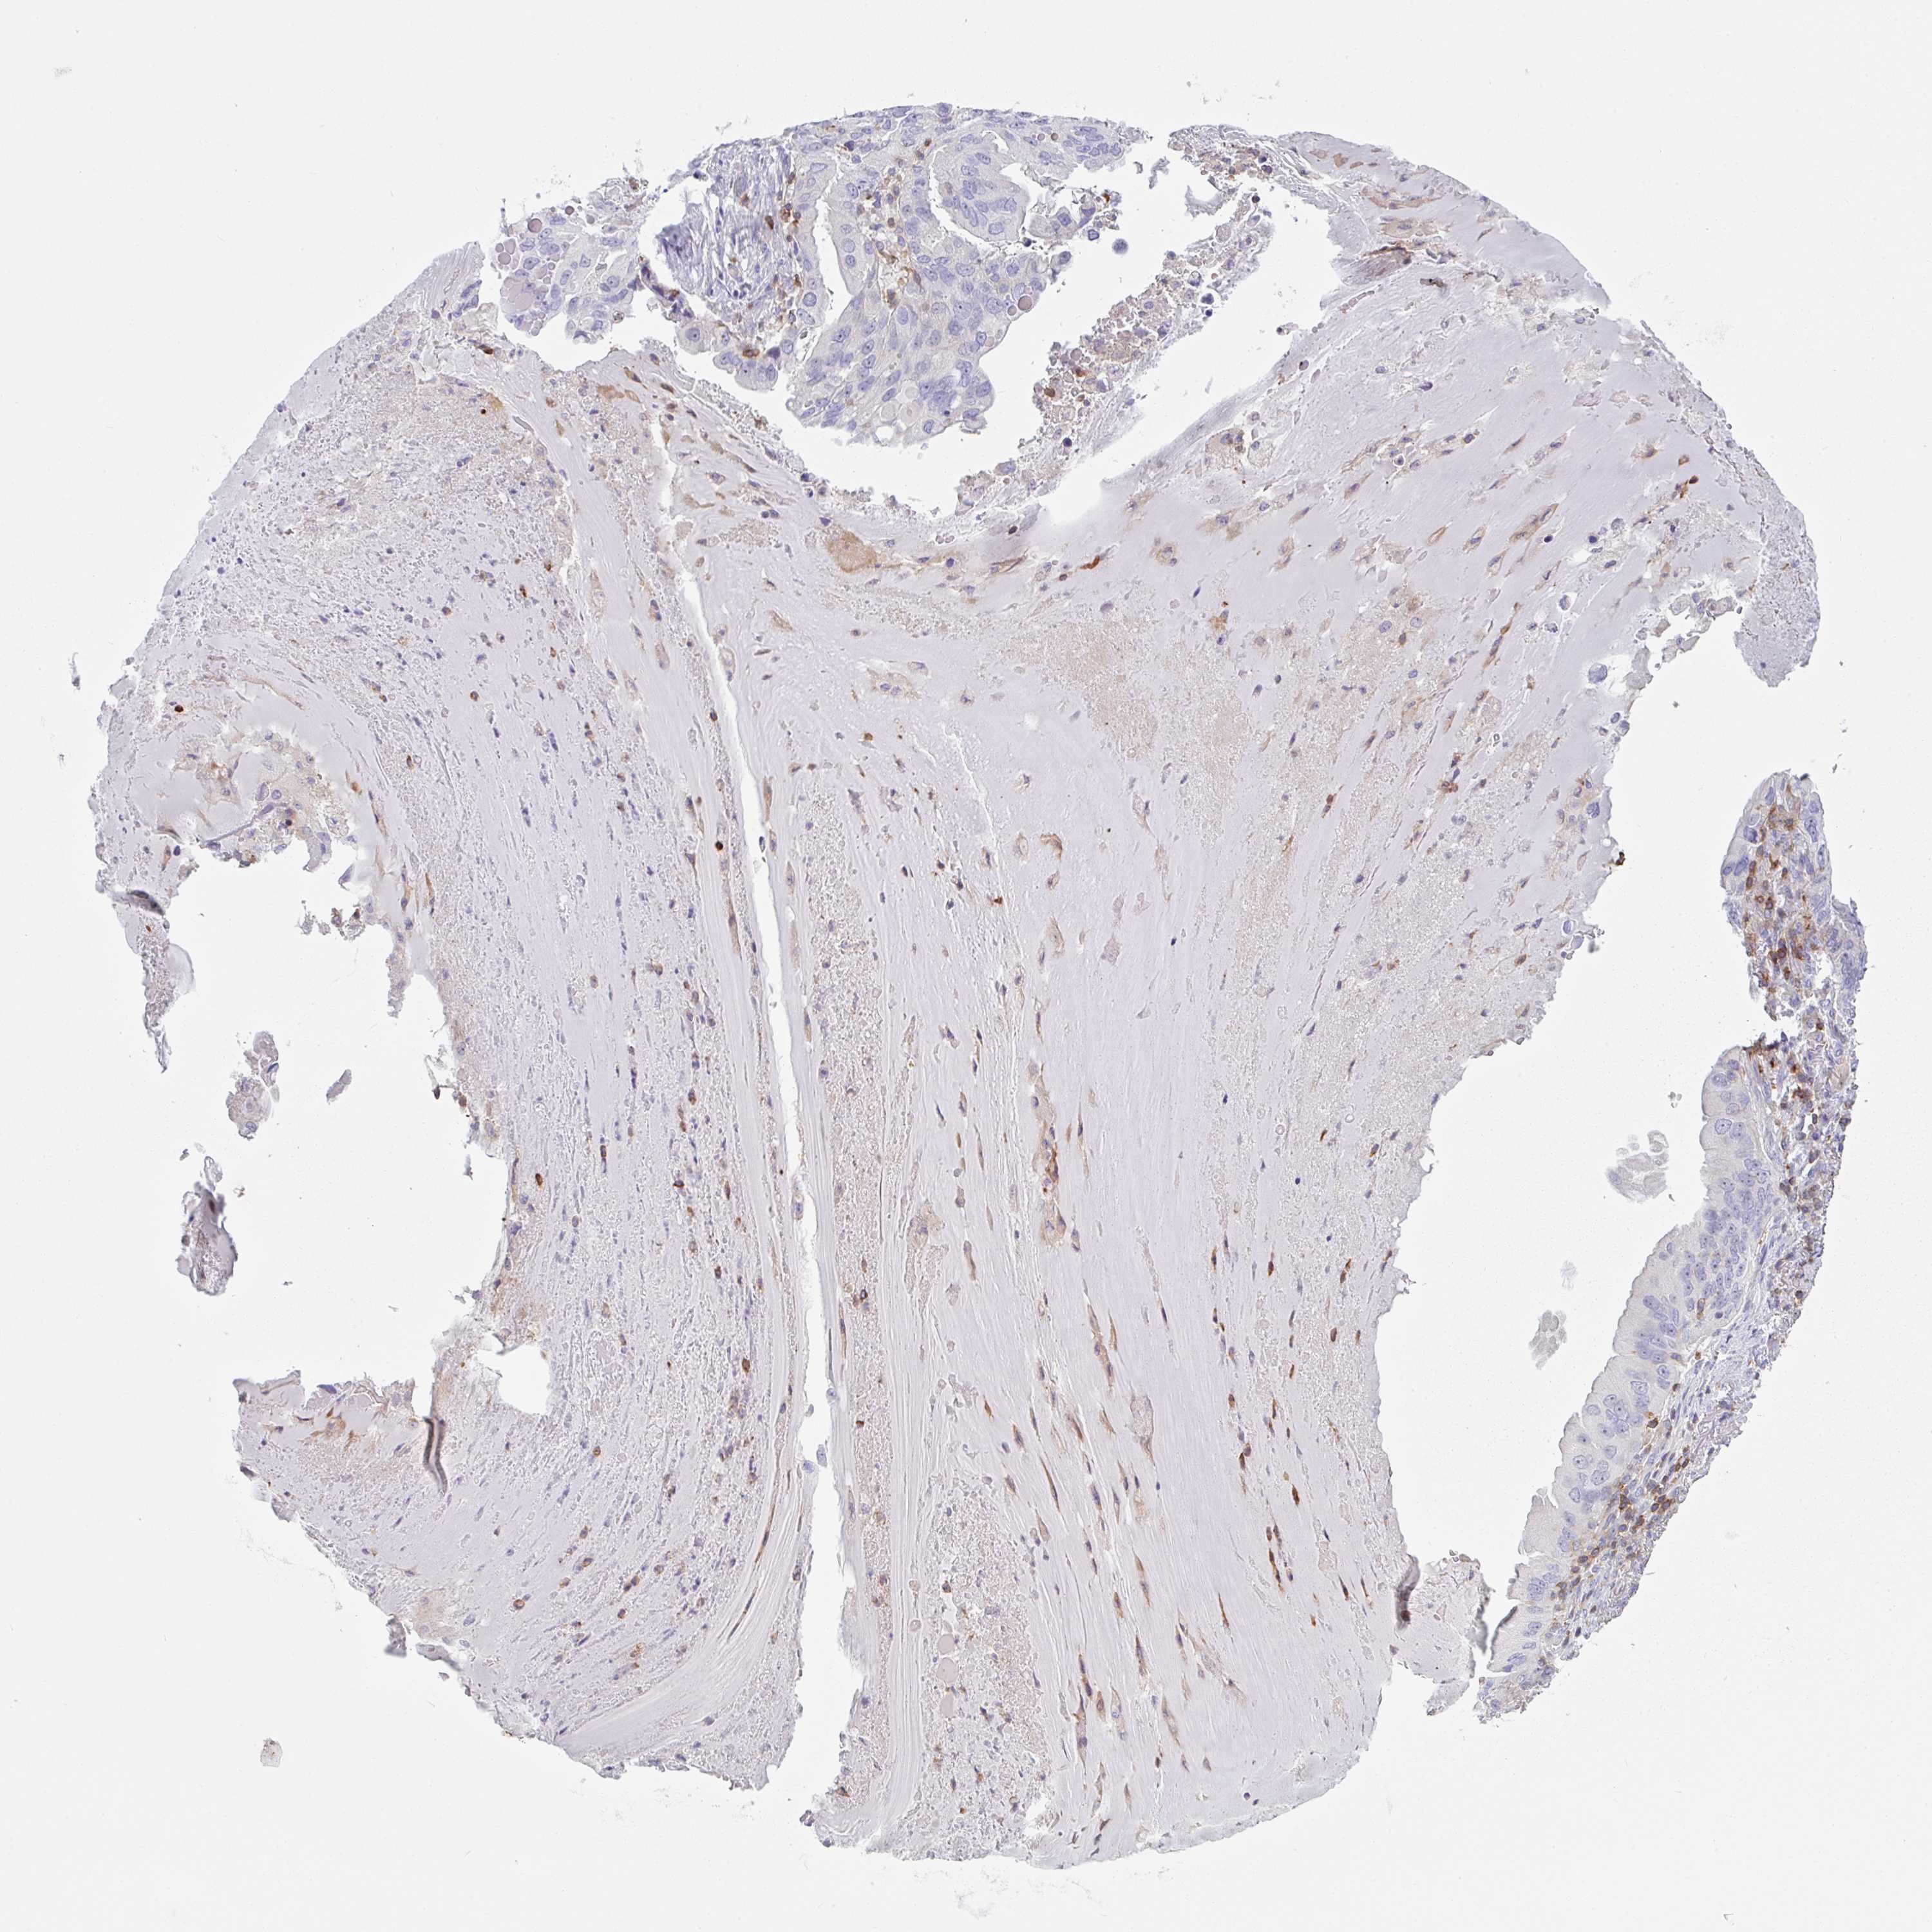

LUNG ADENOCARCINOMA (TCGA) - Interactive survival scatter ploti

The Survival Scatter plot shows the clinical status (i.e. dead or alive) for all individuals in the patient cohort, based on the same data that underlies the corresponding Kaplan-Meier plots. Patients that are alive at last time for follow-up are shown in blue and patients who have died during the study are shown in red.

The x-axis shows the expression levels (FPKM) of the investigated gene in the tumor tissue at the time of diagnosis. The y-axis shows the follow-up time after diagnosis (years). Both axes are complimented with kernel density curves demonstrating the data density over the axes. The top density plot shows the expression levels (FPKM) distribution among dead (red) and alive patients (blue). The right density plot shows the data density of the survived years of dead patients with high and low expression levels respectively, stratified using the cutoff indicated by the vertical dashed line through the Survival Scatter plot. This cutoff is automatically defined based on the FPKM cutoff that minimizes the p-score. The cutoff can be changed by dragging the vertical line or by entering a cutoff value in the square labeled "Current cut-off".

Under the Survival Scatter plot the p-score landscape (black curve; left axis) is shown together with dead median separation (red curve; right axis). Dead median separation is the difference in median mRNA expression between patients who have died with high and low expression, respectively. It is calculated as follows: median FPKM expression of dead patients with high expression - median FPKM expression of dead patients with low expression. This is intended to aid the user in visually exploring custom cutoffs and the associated p-scores and dead median separation.

Individual patient data is displayed and can be filtered by clicking on one or more of the category buttons on the top of the page. Categories describing expression level and patient information include: high, low, alive, dead, female, male and tumor stages. The scale of the x-axis can be toggled between linear and log-scale by clicking on the "x log" button. Mouse-over function shows TCGA ID, patient information and mRNA expression (FPKM) for each patient.

& Survival analysisi

Kaplan-Meier plots summarize results from analysis of correlation between mRNA expression level and patient survival. Patients were divided based on level of expression into one of the two groups "low" (under cut off) or "high" (over cut off). X-axis shows time for survival (years) and y-axis shows the probability of survival, where 1.0 corresponds to 100 percent.

CD80 is not prognostic in Lung Adenocarcinoma (TCGA)

: 1.59

Average pTPM 1.5

Number of samples 497